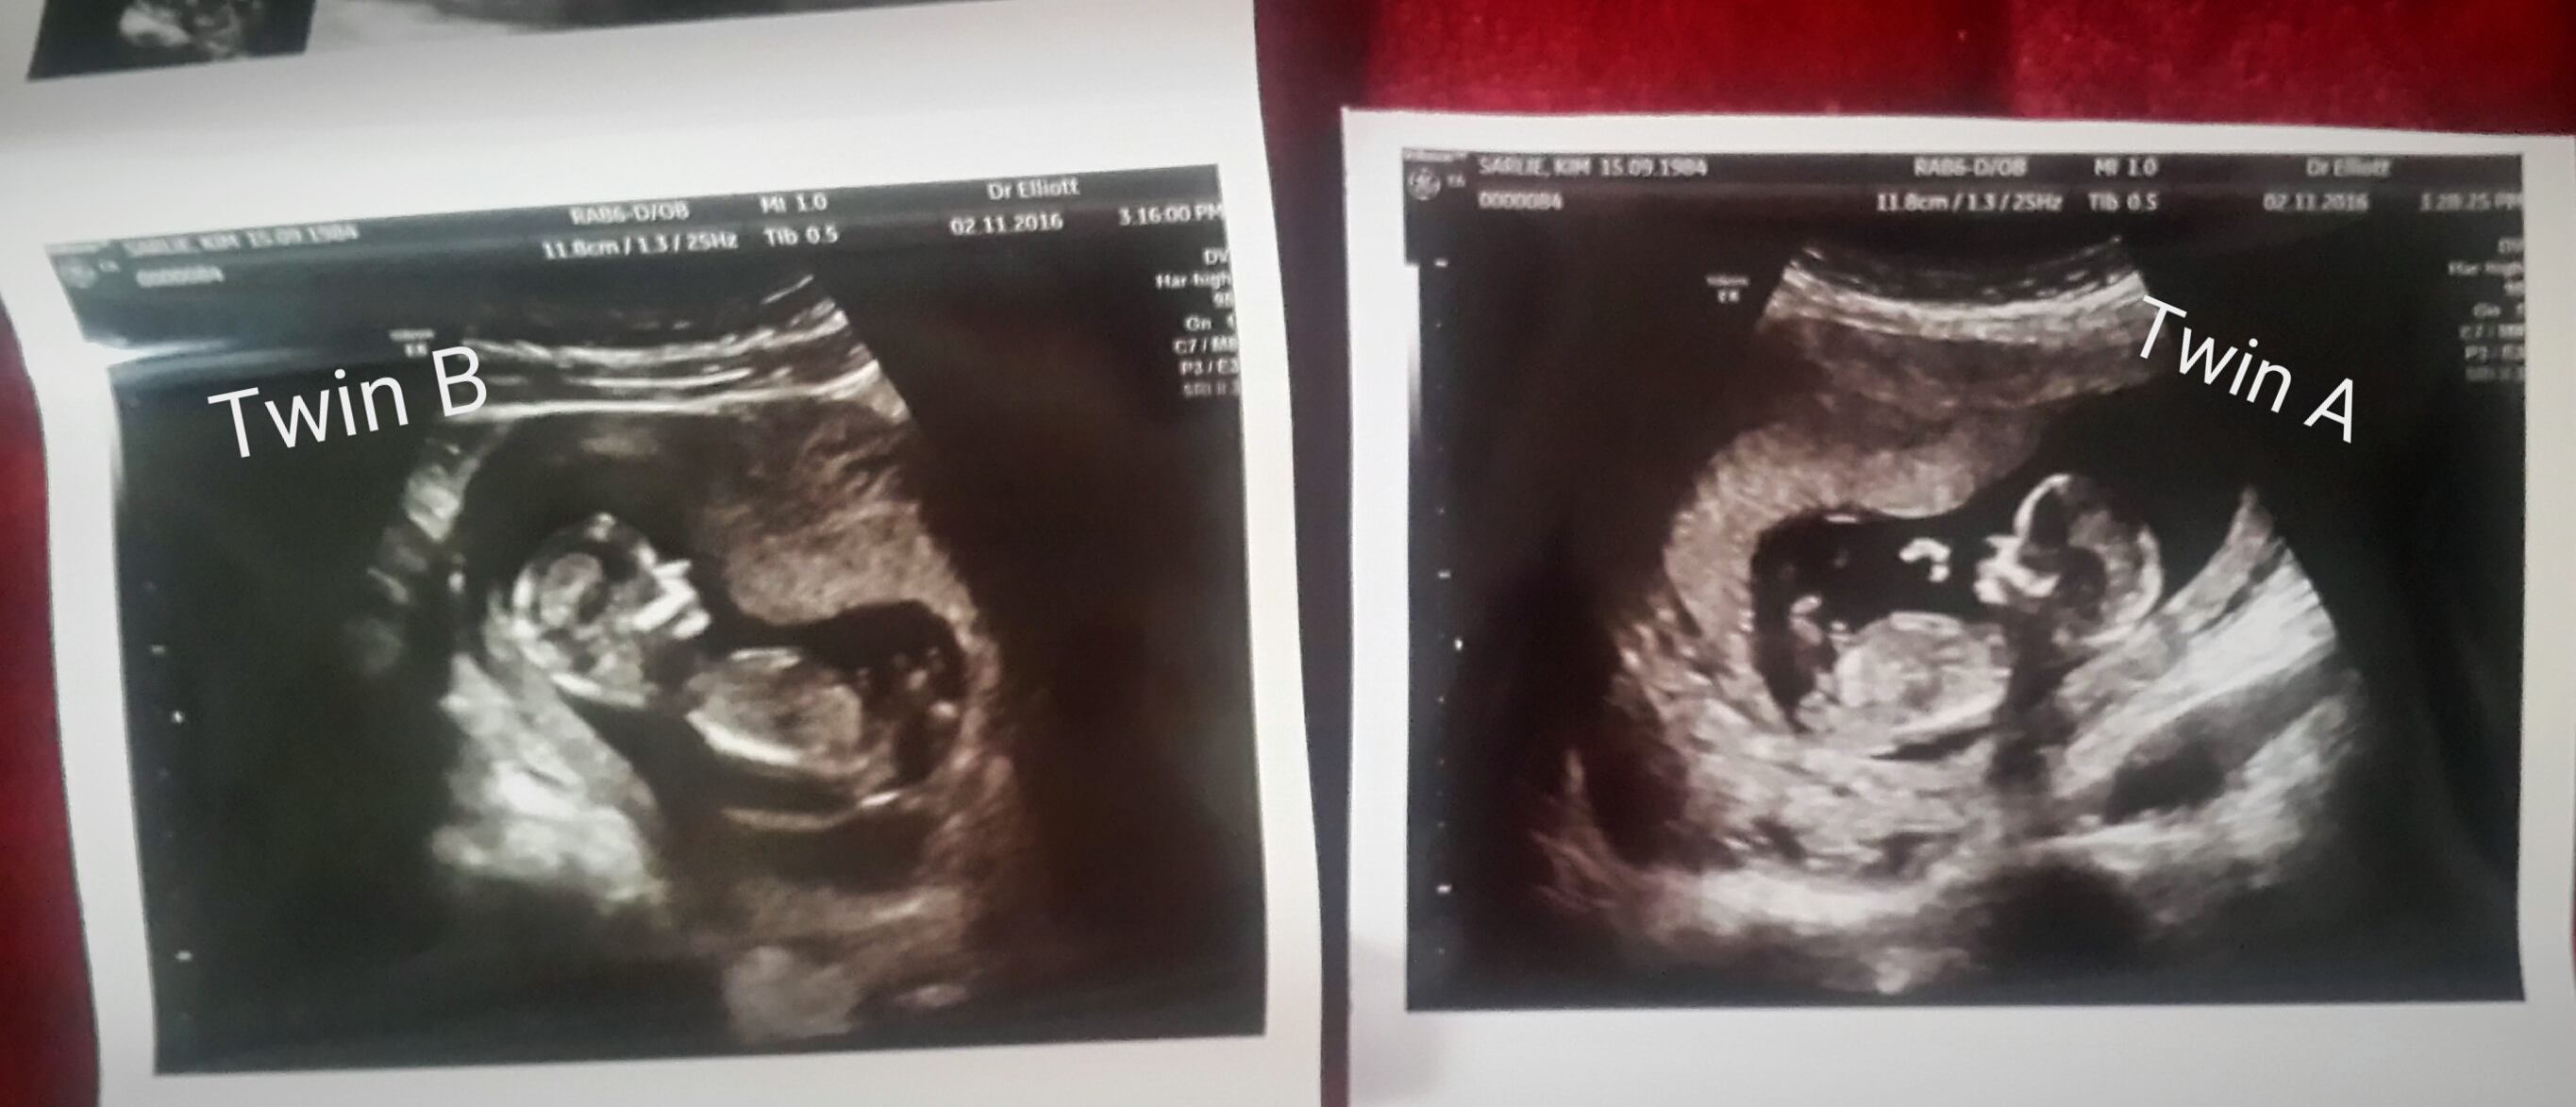

This scan was done at 13w1d and 13w3d. Any gender guesses? Thank youAttachment 33803

Twin A, maybe boy. Twin B, can't tell.

More pics? And it would be great if you could post the pictures separately, they are a bit too small to see properly. Thanks!

Guessing boys:)